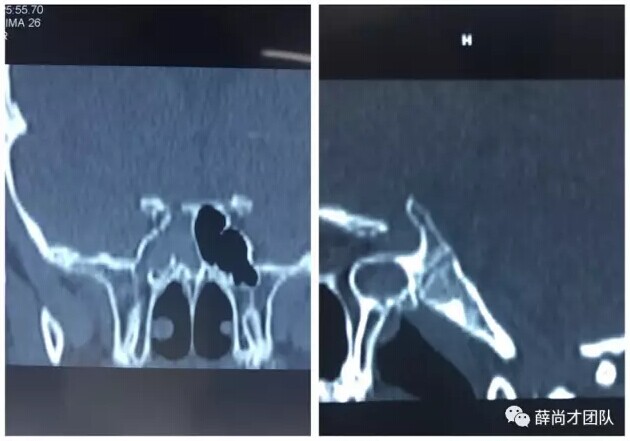

甘肃省二院眼科开展经眼眶视神经减压术使许多外伤失明的患者重见光明------2017-04-28 发布时间:2017-04-28 来源: 作者: